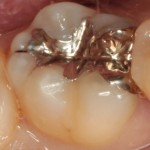

①金属下に虫歯があります

-

②虫歯を取り形を整え、型取りをします

③セラミックスインレーを装着(保険外)